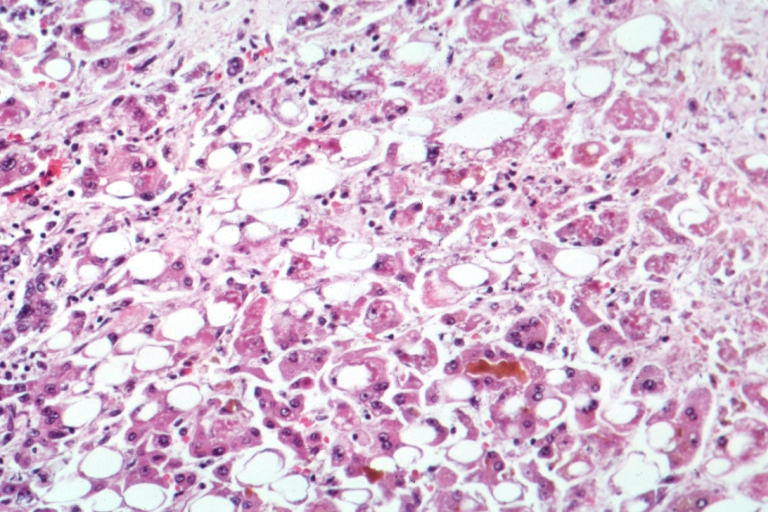

- Алкогольный гепатит развивается при хроническом злоупотреблении спиртными напитками из-за токсического воздействия алкоголя и ацетальдегида (метаболического производного алкоголя) на печень и гепатоциты (клетки печени). Кроме прямого повреждения гепатоцитов, имеет место замедление, а затем и торможение процесса регенерации печени. Алкогольный гепатит может иметь место в двух формах проявления: в обратимой форме, когда возможно излечение (при условии полного отказа от приема алкоголя и при соблюдении соответствующего лечения и диеты), и в виде прогрессирующей формы. При продолжении приема алкоголя наблюдается ухудшение состояния, гепатоциты претерпевают значительные нарушения, которые приводят к их некрозу, к гибели нормальной ткани печени и замене ее фиброзной тканью, к развитию тяжелого поражения — циррозу печени.

В самостоятельном виде инфекционный возбудитель типа G протекает в средней форме без симптомов желтухи, однако редко уходит из организма носителя бесследно. Вирус в корне меняет строение и повреждает клетки печёночной паренхимы, что в дальнейшем способно привести к другим проблемам со здоровьем. Иная точка зрения: вирус таится длительное время в печёночной ткани человека, а затем влечёт серьёзные последствия – цирроз или начальную стадию карциномы печени.